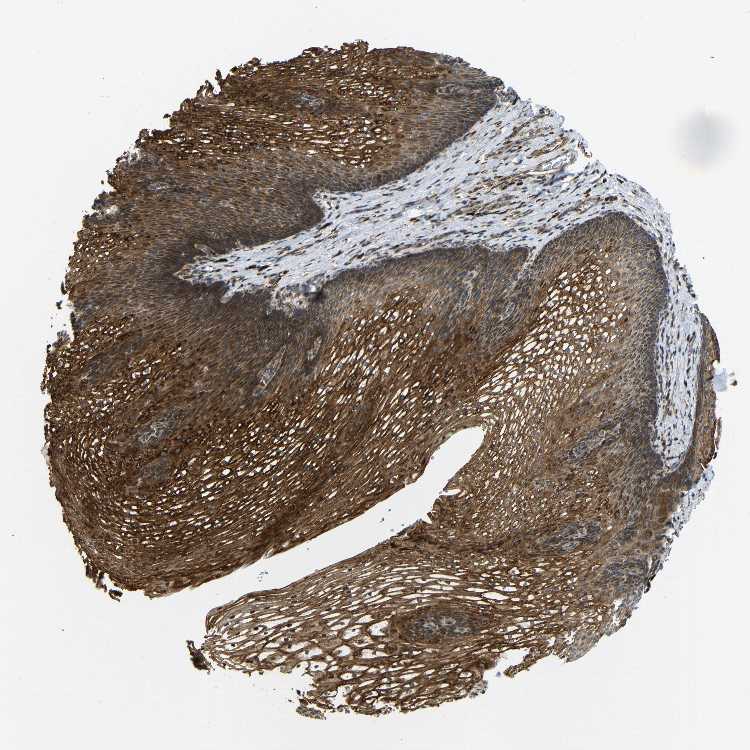

ESOPHAGUS - Antibody stainingi

Antibody staining in the annotated cell types in the current human tissue is reported as not detected, low, medium, or high, based on conventional immunohistochemistry profiling in selected tissues. This score is based on the combination of the staining intensity and fraction of stained cells.

Each image is clickable and will lead to virtual microscopy that enables deeper exploration of all samples and also displays staining intensity scores, fraction scores and subcellular localization as well as patient and tissue information for each sample.

Antibody HPA014030

Squamous epithelial cells High